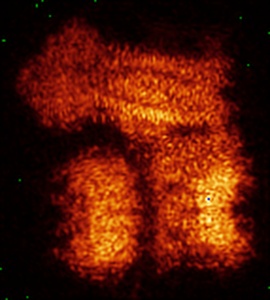

Cryo-EM structure of the pancreatic ATP-sensitive potassium channel bound to ATP and repaglinide with Kir6.2-CTD in the down conformation

Sample: KATP-RPG-ATP-CTDdown

Ligand-mediated Structural Dynamics of a Mammalian Pancreatic K ATP Channel.

Sung MW, Driggers CM , Mostofian B, Russo JD , Patton BL, Zuckerman DM , Shyng SL

(2022) J Mol Biol , 434 , 167789 - 167789